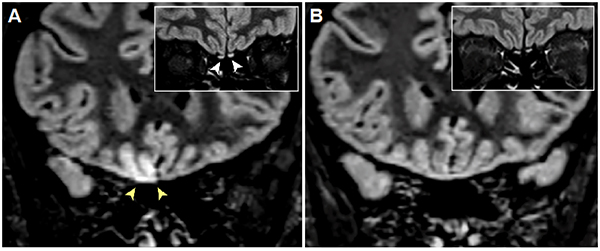

They found that many cases of mild COVID-19 present with cranial nerve abnormalities on neuroimaging, in particular abnormal signal within the olfactory tract in patients experiencing loss of taste and smell. In contrast, more serious conditions such as cerebral hemorrhage and posterior reversible encephalopathy syndrome appeared exclusive to patients who were classified as having severe disease, defined as requiring ICU admission or mechanical ventilation. Surprisingly, ischemic stroke was equally prevalent in both mild and severe cases, suggesting that SARS-CoV-2 virus may have unique coagulopathic properties that predispose to developing strokes even in patients that are not acutely ill.